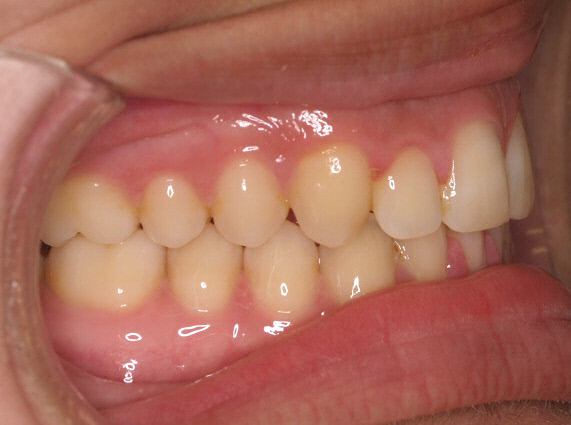

Premolar mandibular incluido + fenestración

45 incluido